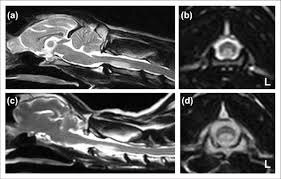

Ишемический инфаркт (типичный “паттерн”)

У кошек с предполагаемым острым инфарктом описаны очаги T1 iso/гипоинтенсивные и T2 гиперинтенсивные, иногда с мягким контраст‑усилением; при отсутствии другой системной патологии FCE рассматривается как вероятная этиология.

Для собак детально описаны МР‑находки у пациентов с предполагаемыми инфарктами/ишемической миелопатией и FCEM.

AVM/AVF (подозрение по МРТ)

Паттерны, заставляющие думать о сосудистой мальформации:

• “серпигинозные” сосудистые структуры/flow‑voids,

• диффузный отёк/миелопатия на фоне венозной гипертензии,

• сопутствующая костная гиперостоз/ангиоматоз (в отдельных фенотипах).

Для собак роль CTA и интервенционной ангиографии описана в конкретном клиническом случае экстрадуральной AVF, а интрамедуллярная AVM описана как антемортем диагностируемая по MRI+CTA.